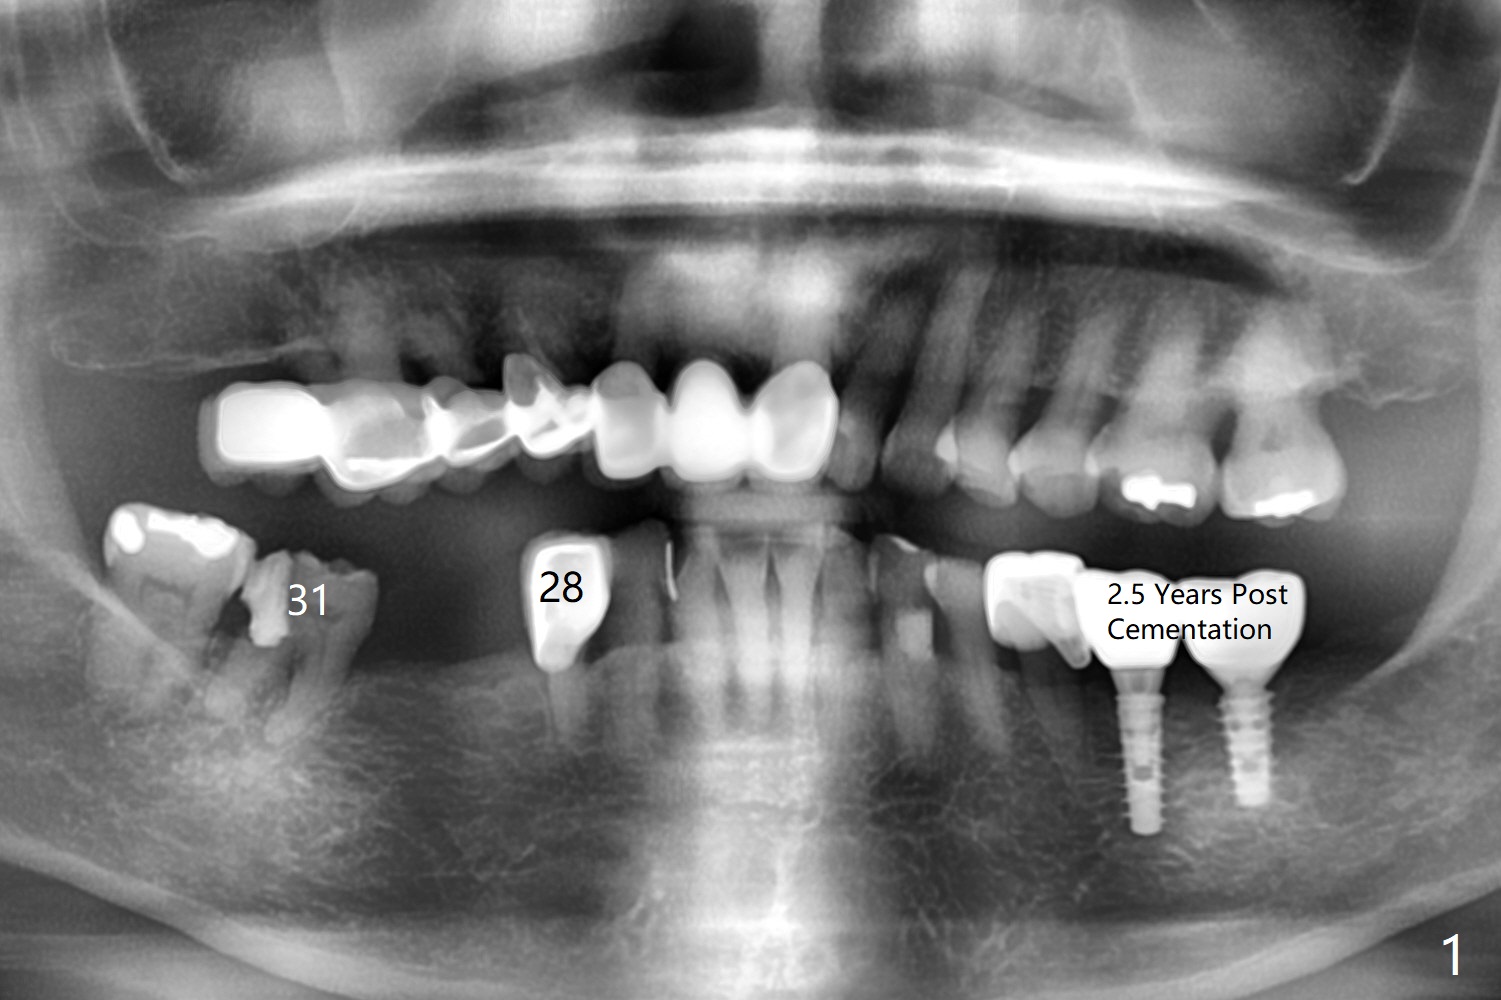

A 71-year-old woman has failed retainer at #31 (Fig.1). Implants will be placed at #31 and 29 for a FPD (Fig.2,3, as compared to Fig.4,5). The ridge at #29 is narrow with thick lingual plate. To avoid buccal deviation, coronal osteotomy overprep will be conducted.